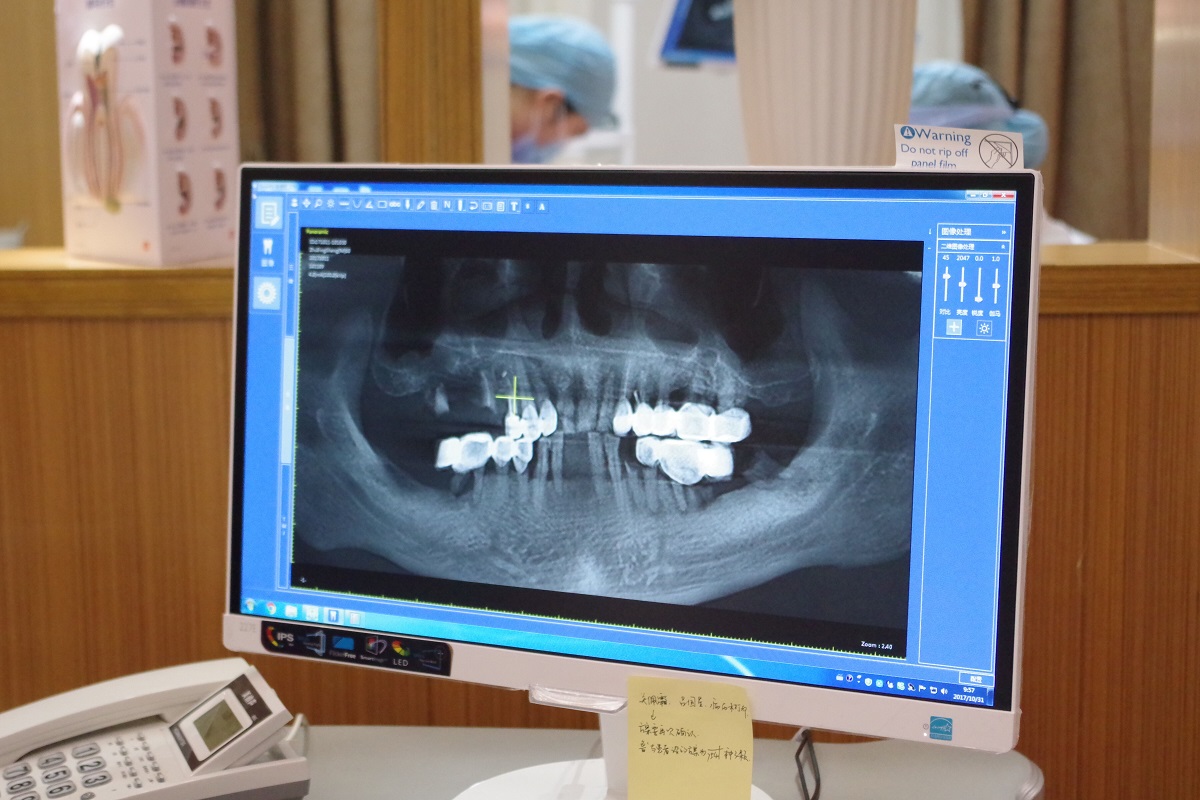

順德德倫口腔醫(yī)院技術(shù)院長林智勇為炳叔設(shè)計(jì)了數(shù)字化種牙方案,并在計(jì)算機(jī)的引導(dǎo)下準(zhǔn)確植入6棵植體。“并非9顆缺牙就要種9顆種植體,采用數(shù)字化種植牙的方式,只給炳叔種了6顆植體,然后通過搭橋的方式實(shí)現(xiàn)9顆牙齒的作用,避免每一個(gè)牙位都種植的缺陷,也能讓老人家少受痛苦。”林智勇解釋道。